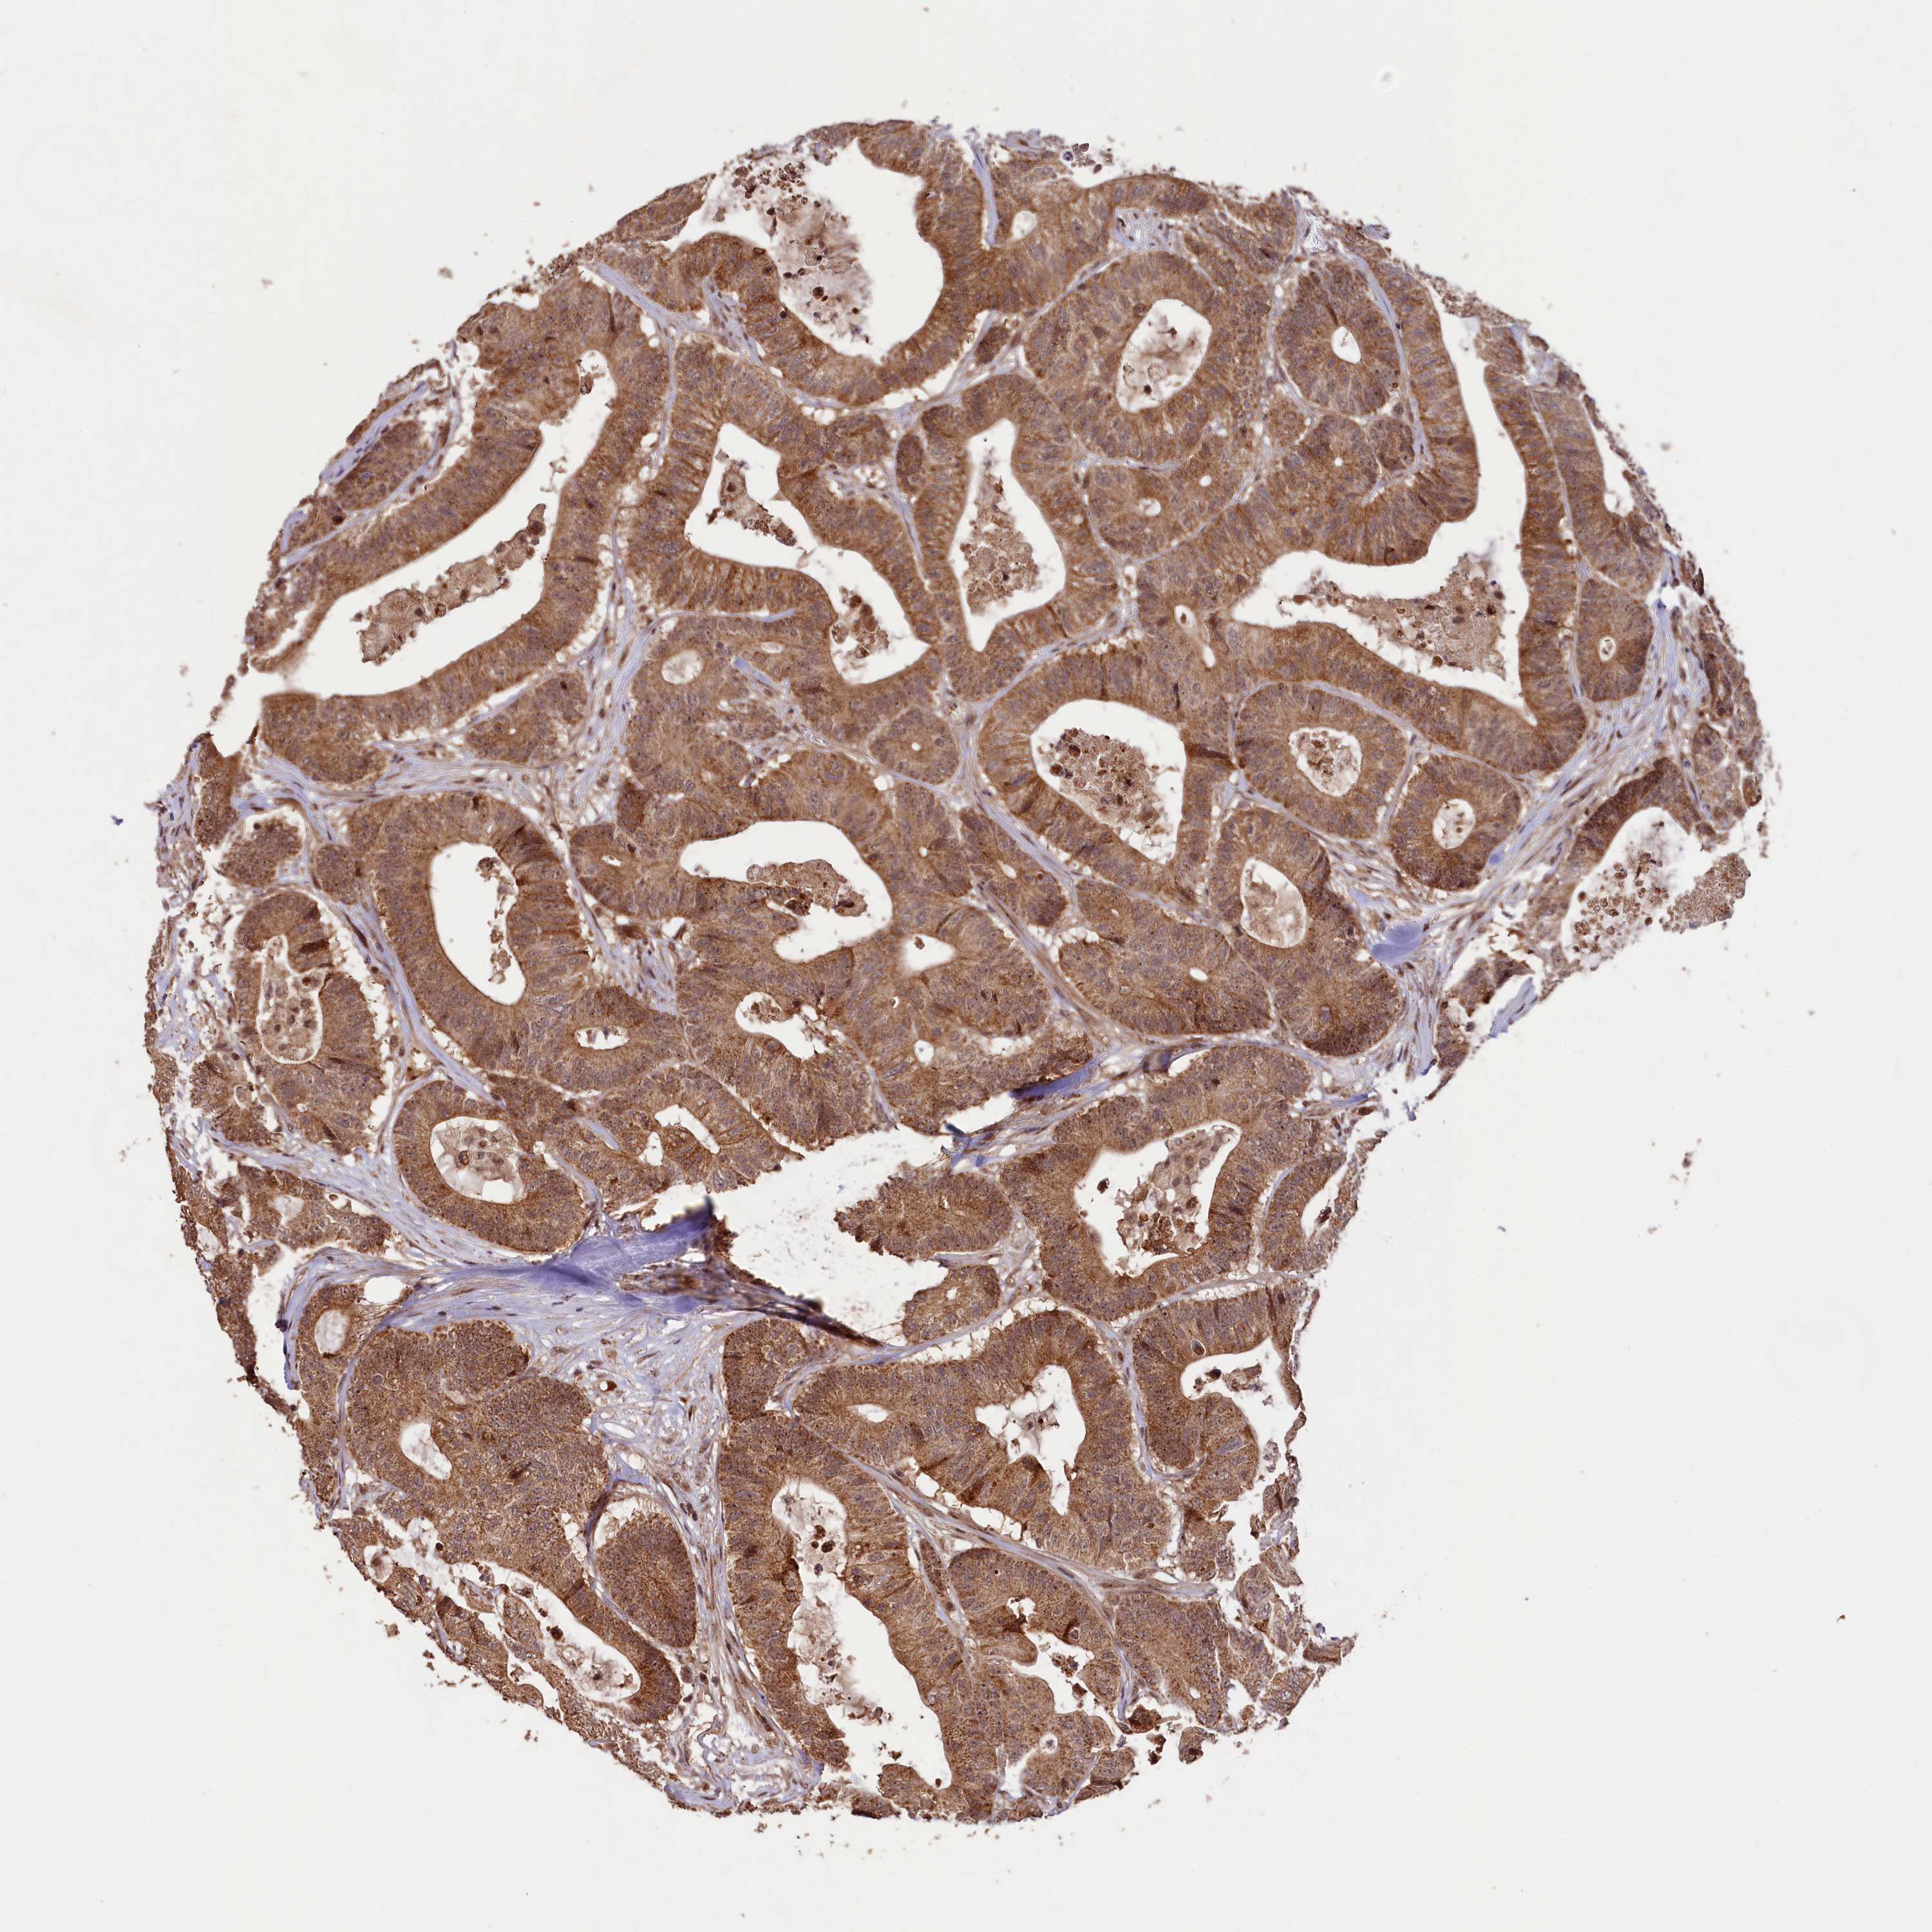

Colorectal cancer

Colon adenocarcinoma